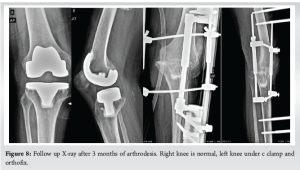

Three months after her second surgery, the patient presented with a deformity on the left side, which was diagnosed as an atraumatic posterior knee dislocation (Fig. 6). The right side was normal but stiff. Immediate reduction was performed under sedation in the operating room, followed by immobilization using an above-knee plaster slab with side support. A periprosthetic joint infection workup was conducted. The patient had a UTI due to a catheter inserted by a local physician, and her blood tests showed low hemoglobin levels of 6 g%. She was treated with intravenous antibiotics and blood transfusion. Comprehensive neurological and hormonal evaluations revealed late-onset Parkinson’s disease with Alzheimer’s traits. Follow-up X-rays indicated an unstable left knee, for which revision with a constrained implant was recommended. However, due to financial constraints and the patient’s uncooperative nature, knee arthrodesis using a Charnley clamp and Ortho fix was chosen to address the unstable left knee dislocation. During the procedure, no signs of infection were observed, but hamstring tightness was noted. The surgical team thoroughly cleaned the area with pulse lavage, removed the implant, freshened the edges, and achieved arthrodesis (Fig. 7). The infection work up did not yield result. At the 3-month follow-up, the patient had a pain-free, arthrosed left knee and a stable right knee with a range of motion from 5° to 100°, without any neuromuscular deficits (Fig. 8).